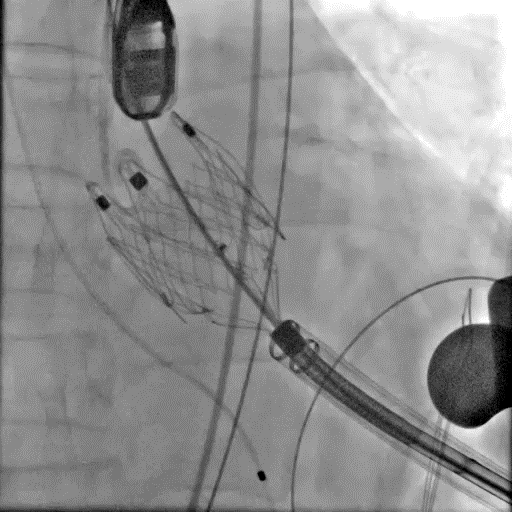

进输送器

定位键入窦

瓣膜释放

术后造影